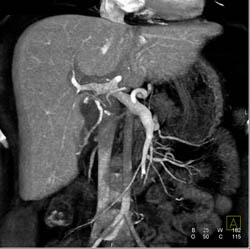

Cholangiocarcinoma